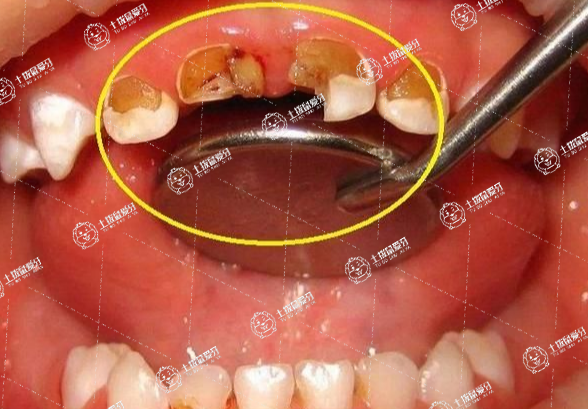

不注意刷牙,衛(wèi)生習(xí)慣不好,愛(ài)吃零食等等都是很多人出現(xiàn)牙齒問(wèn)題的一個(gè)非常重要的因素,年齡不大的話,如果出現(xiàn)蛀牙的話,往往就會(huì)給自身身心健康造成非常巨大的傷害,因此,大多數(shù)家長(zhǎng)都會(huì)想辦法及時(shí)做拔牙修復(fù)處理,拔牙用的麻藥對(duì)懷孕有影響嗎?接下來(lái),我們一起來(lái)了解一下。